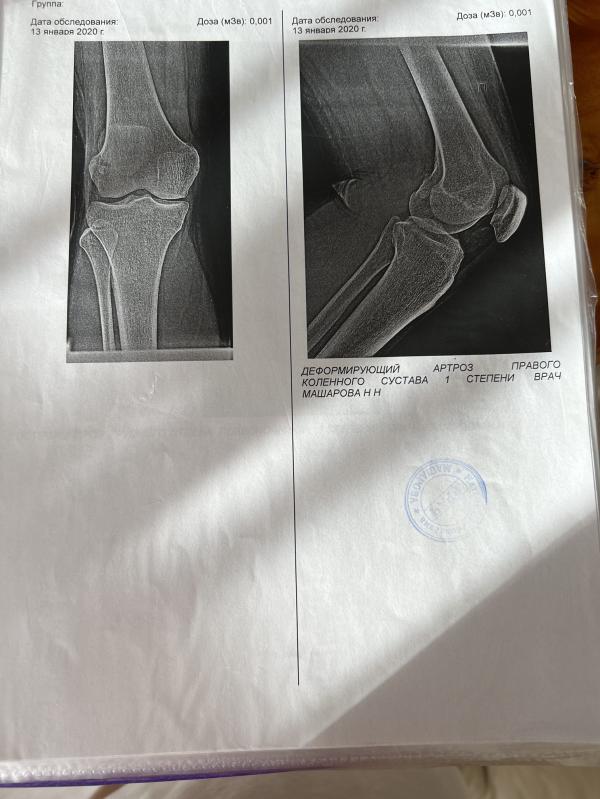

Может быть вы или ваши знакомые сталкивались с диагнозом «деформирующий артроз колена»?В чем собственно суть…диагноз мне поставили ещё в 2020 оно изредка при больших нагрузках побаливало 😖но решила тогда особо не заморачиваться 1 ж степень….

А вот сейчас в моем интересного положения эта ситуация усугубилась очень очень сильно😫ночью просыпаюсь от дикой боли,днем ходить не могу много и долго,про фитнес вообще забыла….

К врачу идти сейчас бессмысленно …снимки сделать нель...